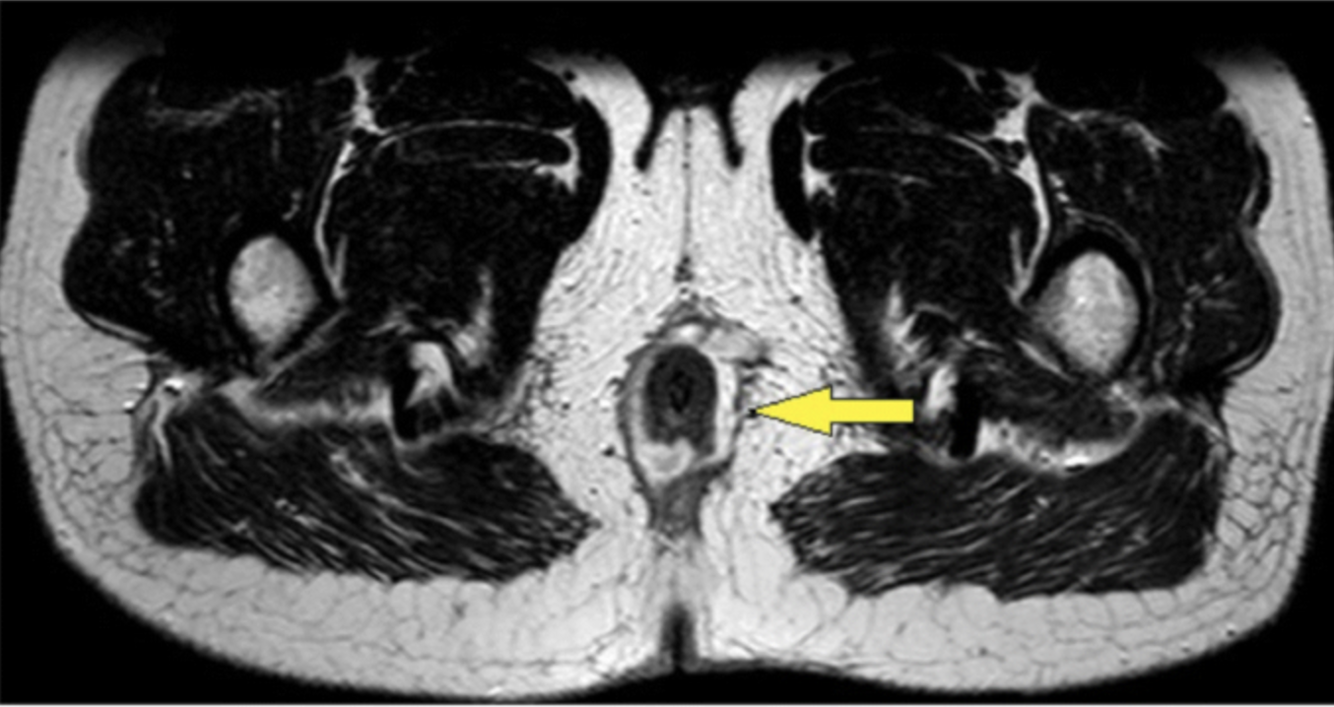

a tender mass may be palpable on DRE of the rectal canal, often in the posterior midline

A

intersphincteric abscess

- pain is also aggravated by straining or coughing

Intersphincteric abscess encircling the rectum (Garg, 2019)